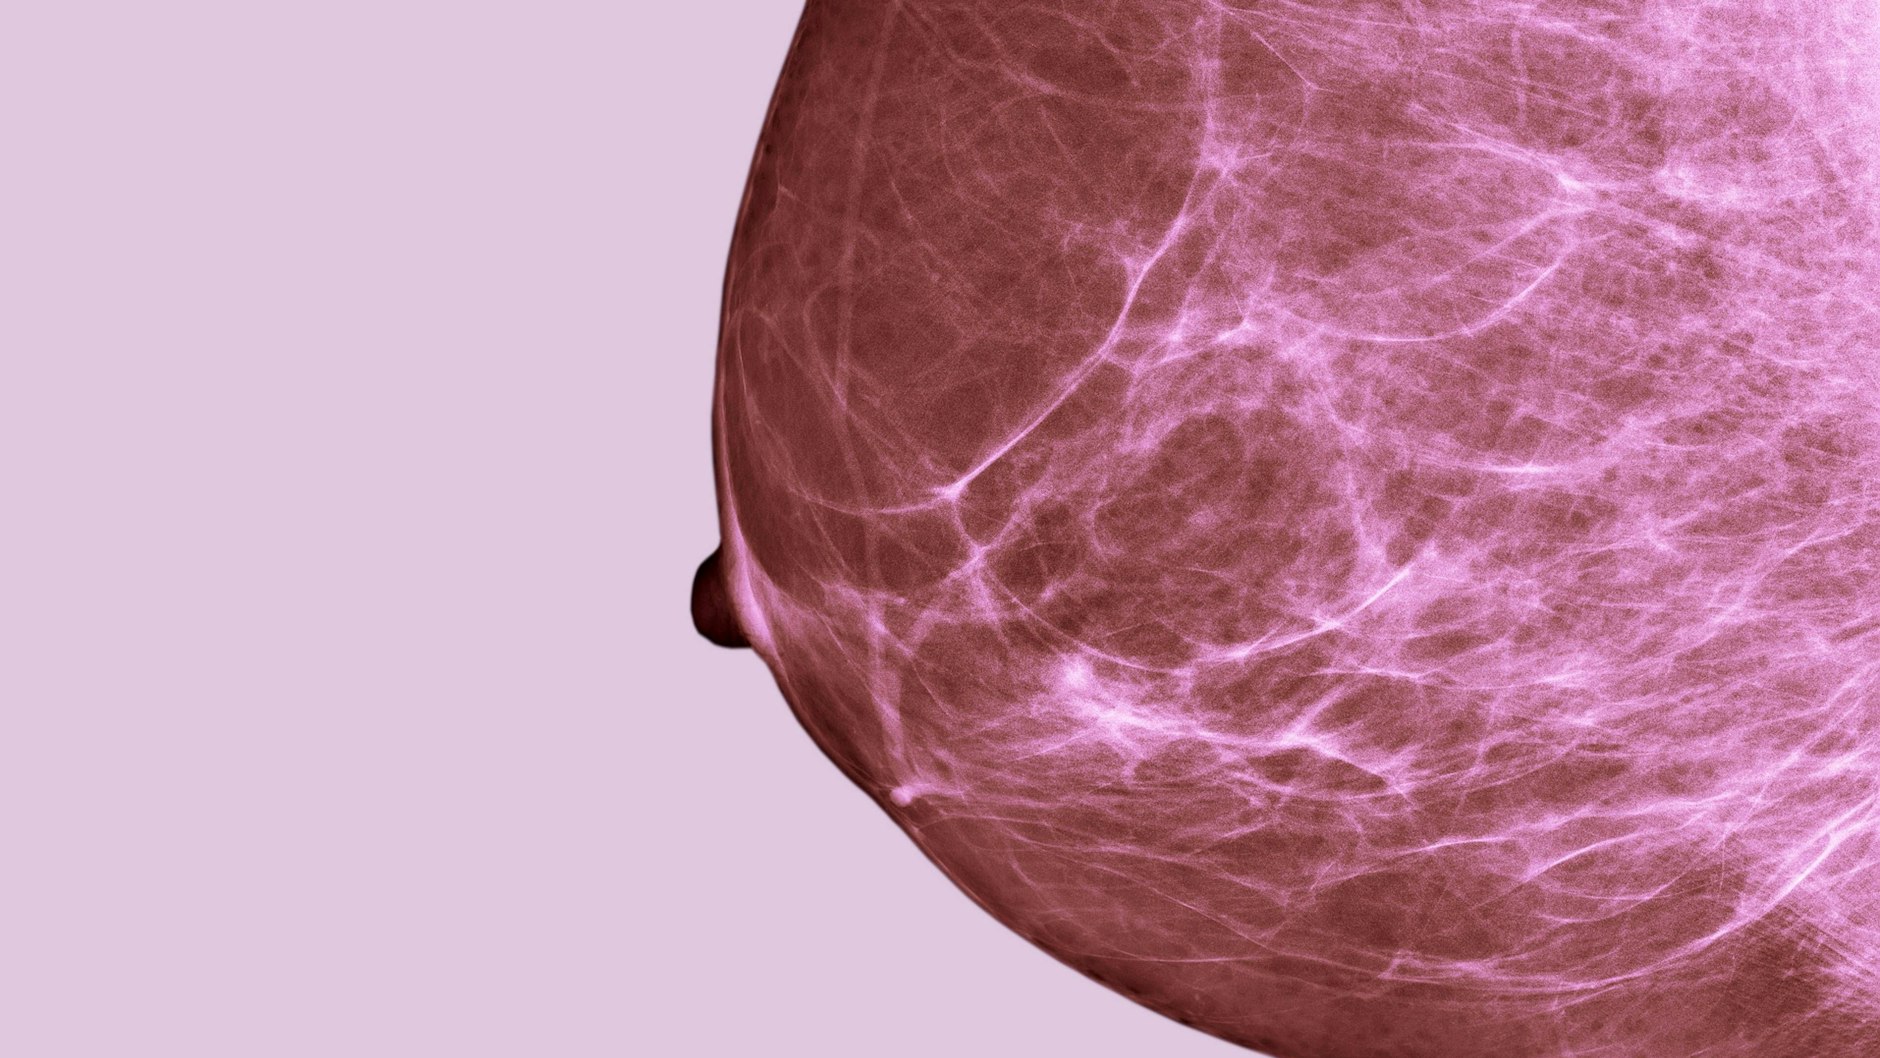

Berlin-Ab einem gewissen Alter ist es wichtig und sinnvoll, gezielt nach Veränderungen im Brustbereich Ausschau zu halten, sagt die Frauenärztin Simone Wesselmann von der Deutschen Krebsgesellschaft in Berlin. „Einer Frau unter 30 würde ich allerdings nicht raten, jeden Monat Brust und Achselhöhlen abzutasten.“ Viel wichtiger findet sie es, dass die Frauenärztin regelmäßig kontrolliert. Das gesetzliche Früherkennungsprogramm bietet Frauen ab 30 Jahren die Möglichkeit einer jährlichen Tastuntersuchung beim Arzt. „Jüngere Patientinnen können das Abtasten aber auch einfordern.“ Die wichtigsten Fragen und Antworten zur Diagnose und Therapie bei Brustkrebs.